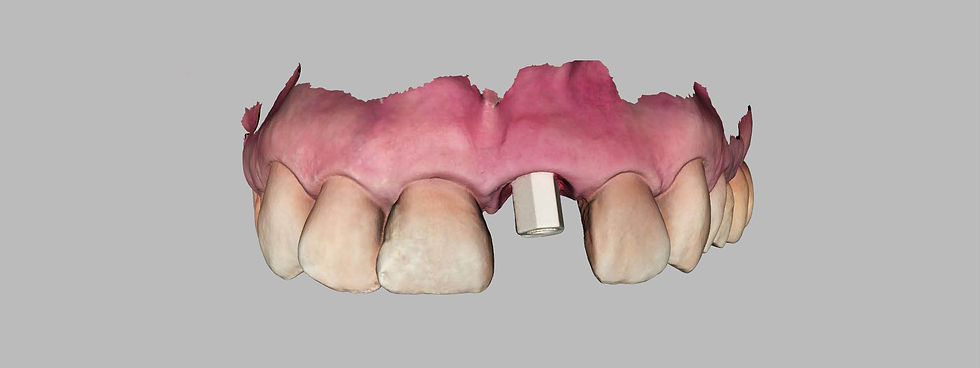

A digital impression is taken with an intraoral scanbody in PEEK.

Intraoral impression acquired by software.